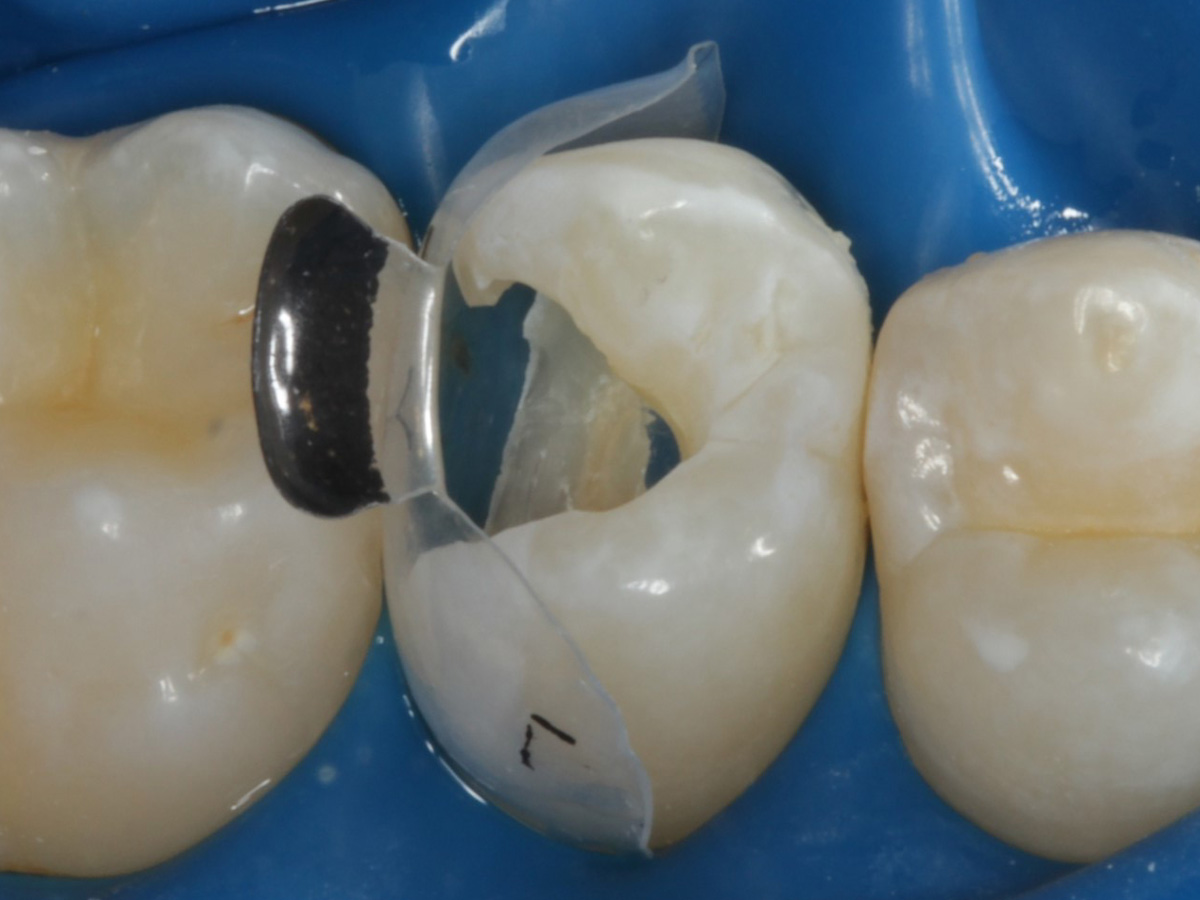

Abbildung 17

Starke Separation der Zähne durch hohe Spannkraft des Twinrings für strammen Kontaktpunkt

Abbildung 18

Bewusst kein Keil zur Vermeidung unerwünschter Matrizenverdrückung